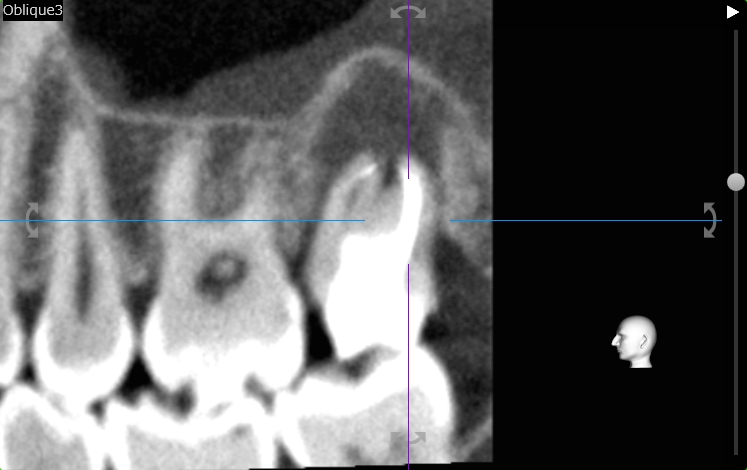

術前のCT画像です。

病変が大きく、患者さんは腫れるとおっしゃっていました。

根管の形はある程度維持されており、根管の先端まで器具を通しさせすれば洗浄は可能のように見えた

画面向かって左側の根管の先端に確認できる白い物体が、以前治療に際して使用された歯科用のファイルだった場合、

ファイルを除去しないと先端まで器具を通すことができない。

病変がそれなりに大きく、歯周病にまで発展している(エンド・ペリオ病変と言います)

しかし今回の第2大臼歯はそれら3本の根っこが融合しており、細かく繋がっておりました。歯科では桶状根と表現されます。

下顎の第2大臼歯では桶状根は良く見られ日常的に遭遇するのですが、上顎の桶状根は初めてでした。